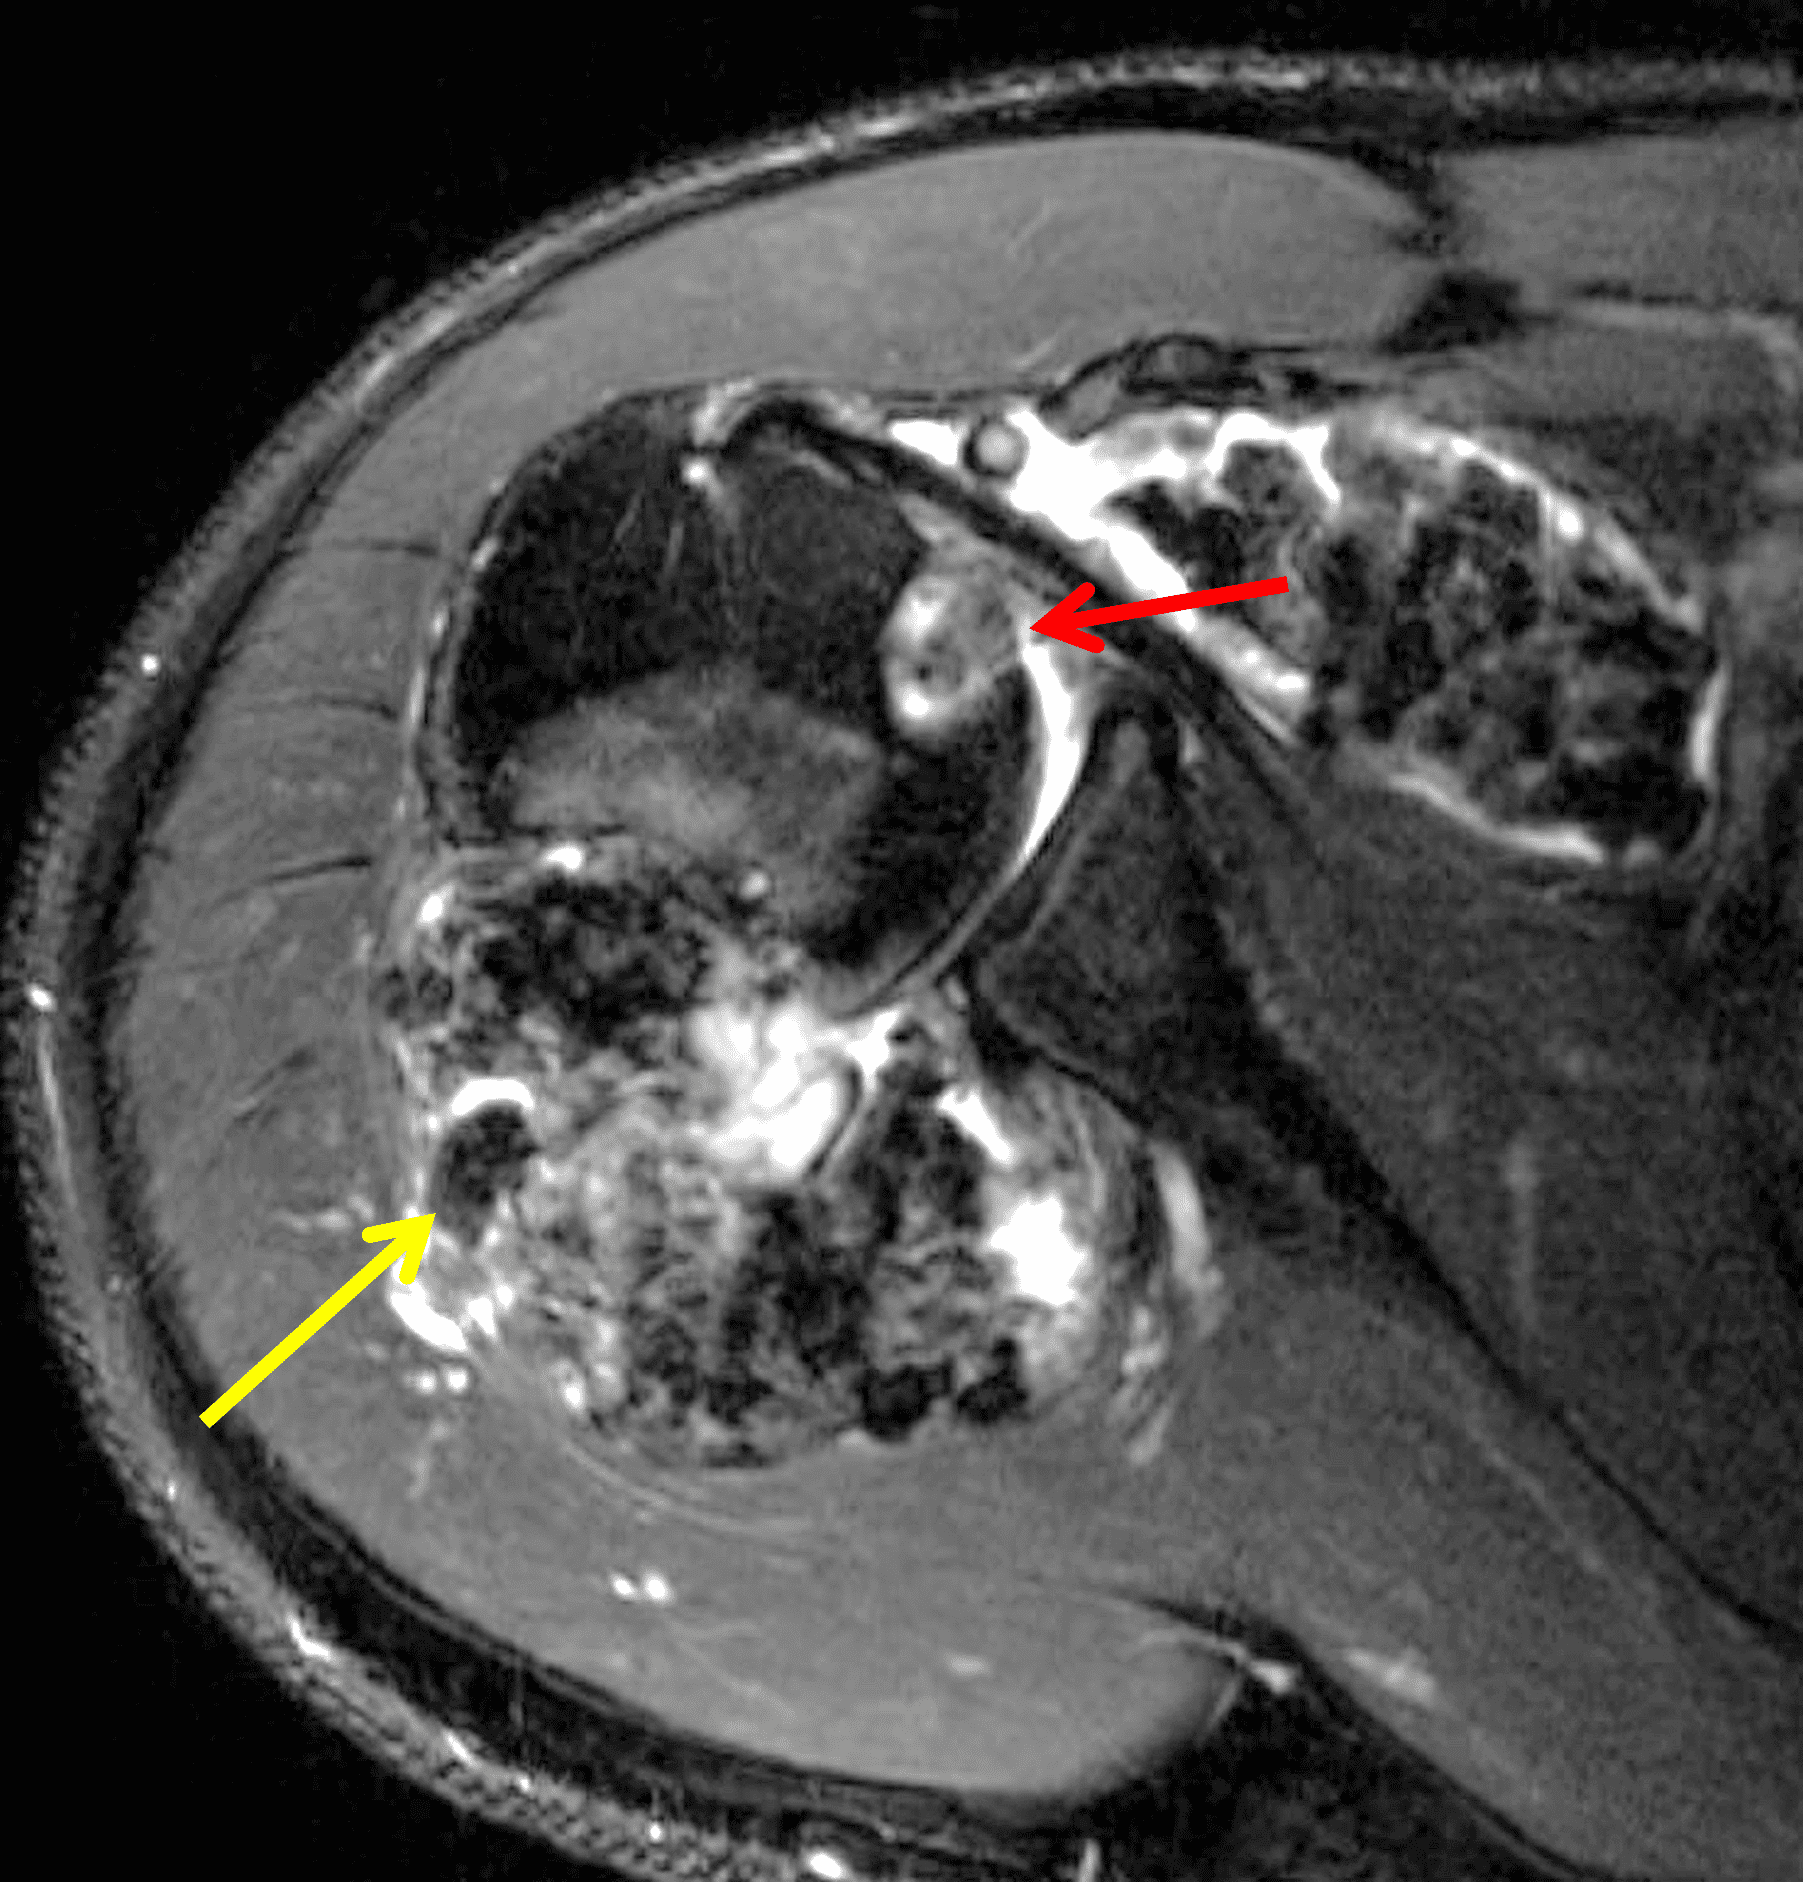

Figure 6: Primary synovial chondromatosis in the shoulder joint. Fat-suppressed fluid-sensitive (6A) axial and (6B) sagittal images, and (6C) sagittal T1-weighted image demonstrate diffuse, lobulated synovially-based heterogeneous masses. T2 hyperintense and intermediate T1 signal areas reflect chondroid matrix (red arrows). T1 and T2 hypointense foci reflect calcification (yellow arrows). T2 hypointense and T1 hyperintense foci reflect areas of endochondral ossification (blue arrows). (6D) Axial CT image shows calcification and ossification in the synovial masses, as well as osseous erosions (arrows).